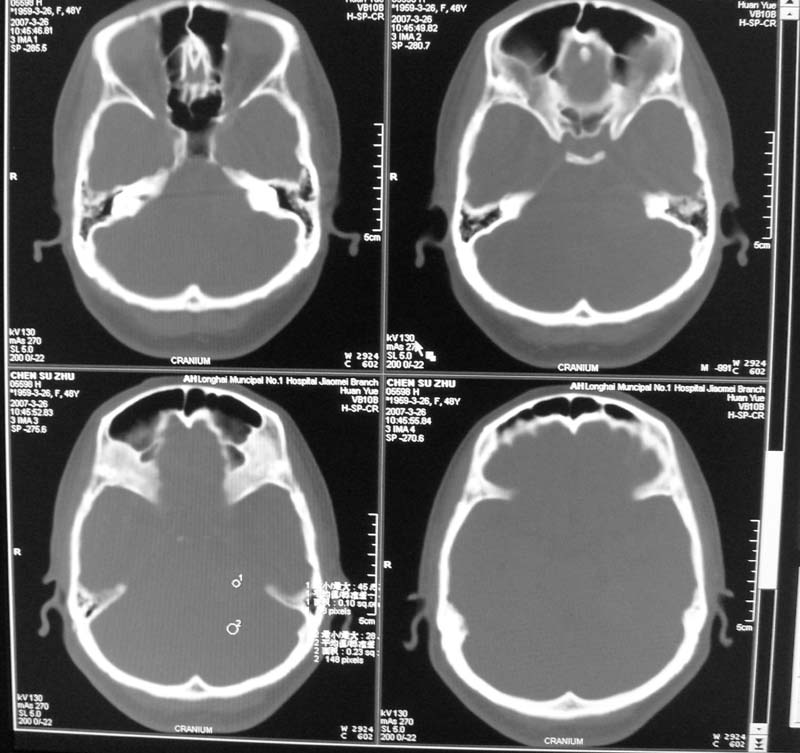

骨窗示内听道未见明显扩大,局部骨质未见明显吸收破坏,

跨颅窝生长,左侧岩骨“刀切样骨质破坏”高度提示三叉神经瘤!

左侧桥小脑角区高密度肿块,周围无水肿及明显占位效应,岩骨尖受压吸收,内听道未见扩大,无听力异常,右侧颅骨外板高密度影,边缘锐利,考虑:左侧脑膜瘤,右侧颅骨骨瘤。左侧岩骨尖有破坏,三叉神经瘤待排。